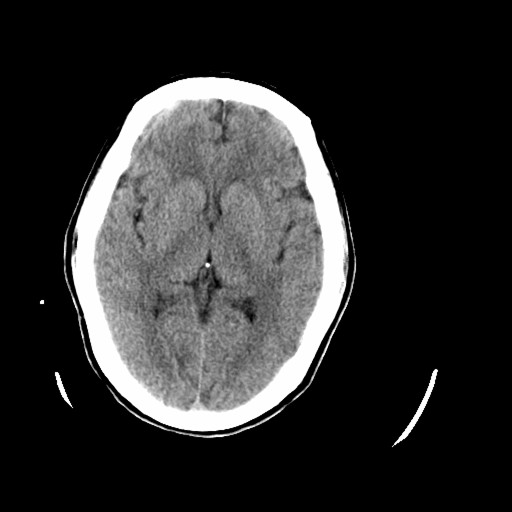

标题: CT16233:女,44岁,智障多年,现感头痛 [打印本页]

标题: CT16233:女,44岁,智障多年,现感头痛

小脑有啥病变?

橄榄桥小脑萎缩.左侧小脑脚腔梗.

1)小脑萎缩。2)小脑蚓部发育不良。

橄榄桥小脑萎缩可能,建议mri进一步检查以进一步排查。

橄榄桥小脑萎缩